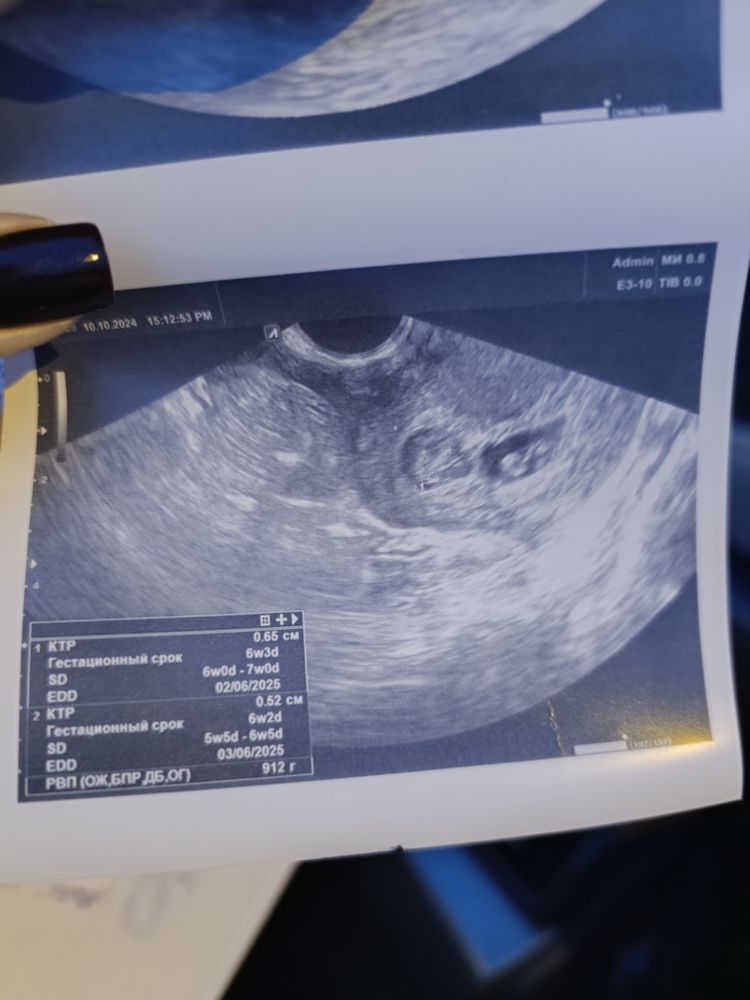

Тройня (2+1)